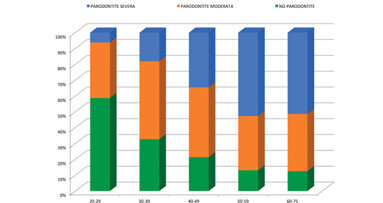

Risultati della prima ricerca epidemiologica in Italia secondo le linee guida dei Centers for Disease Control and Prevention e dell’American Academy ...

Risultati della prima ricerca epidemiologica in Italia secondo le linee guida dei Centers for Disease Control and Prevention e dell’American Academy ...